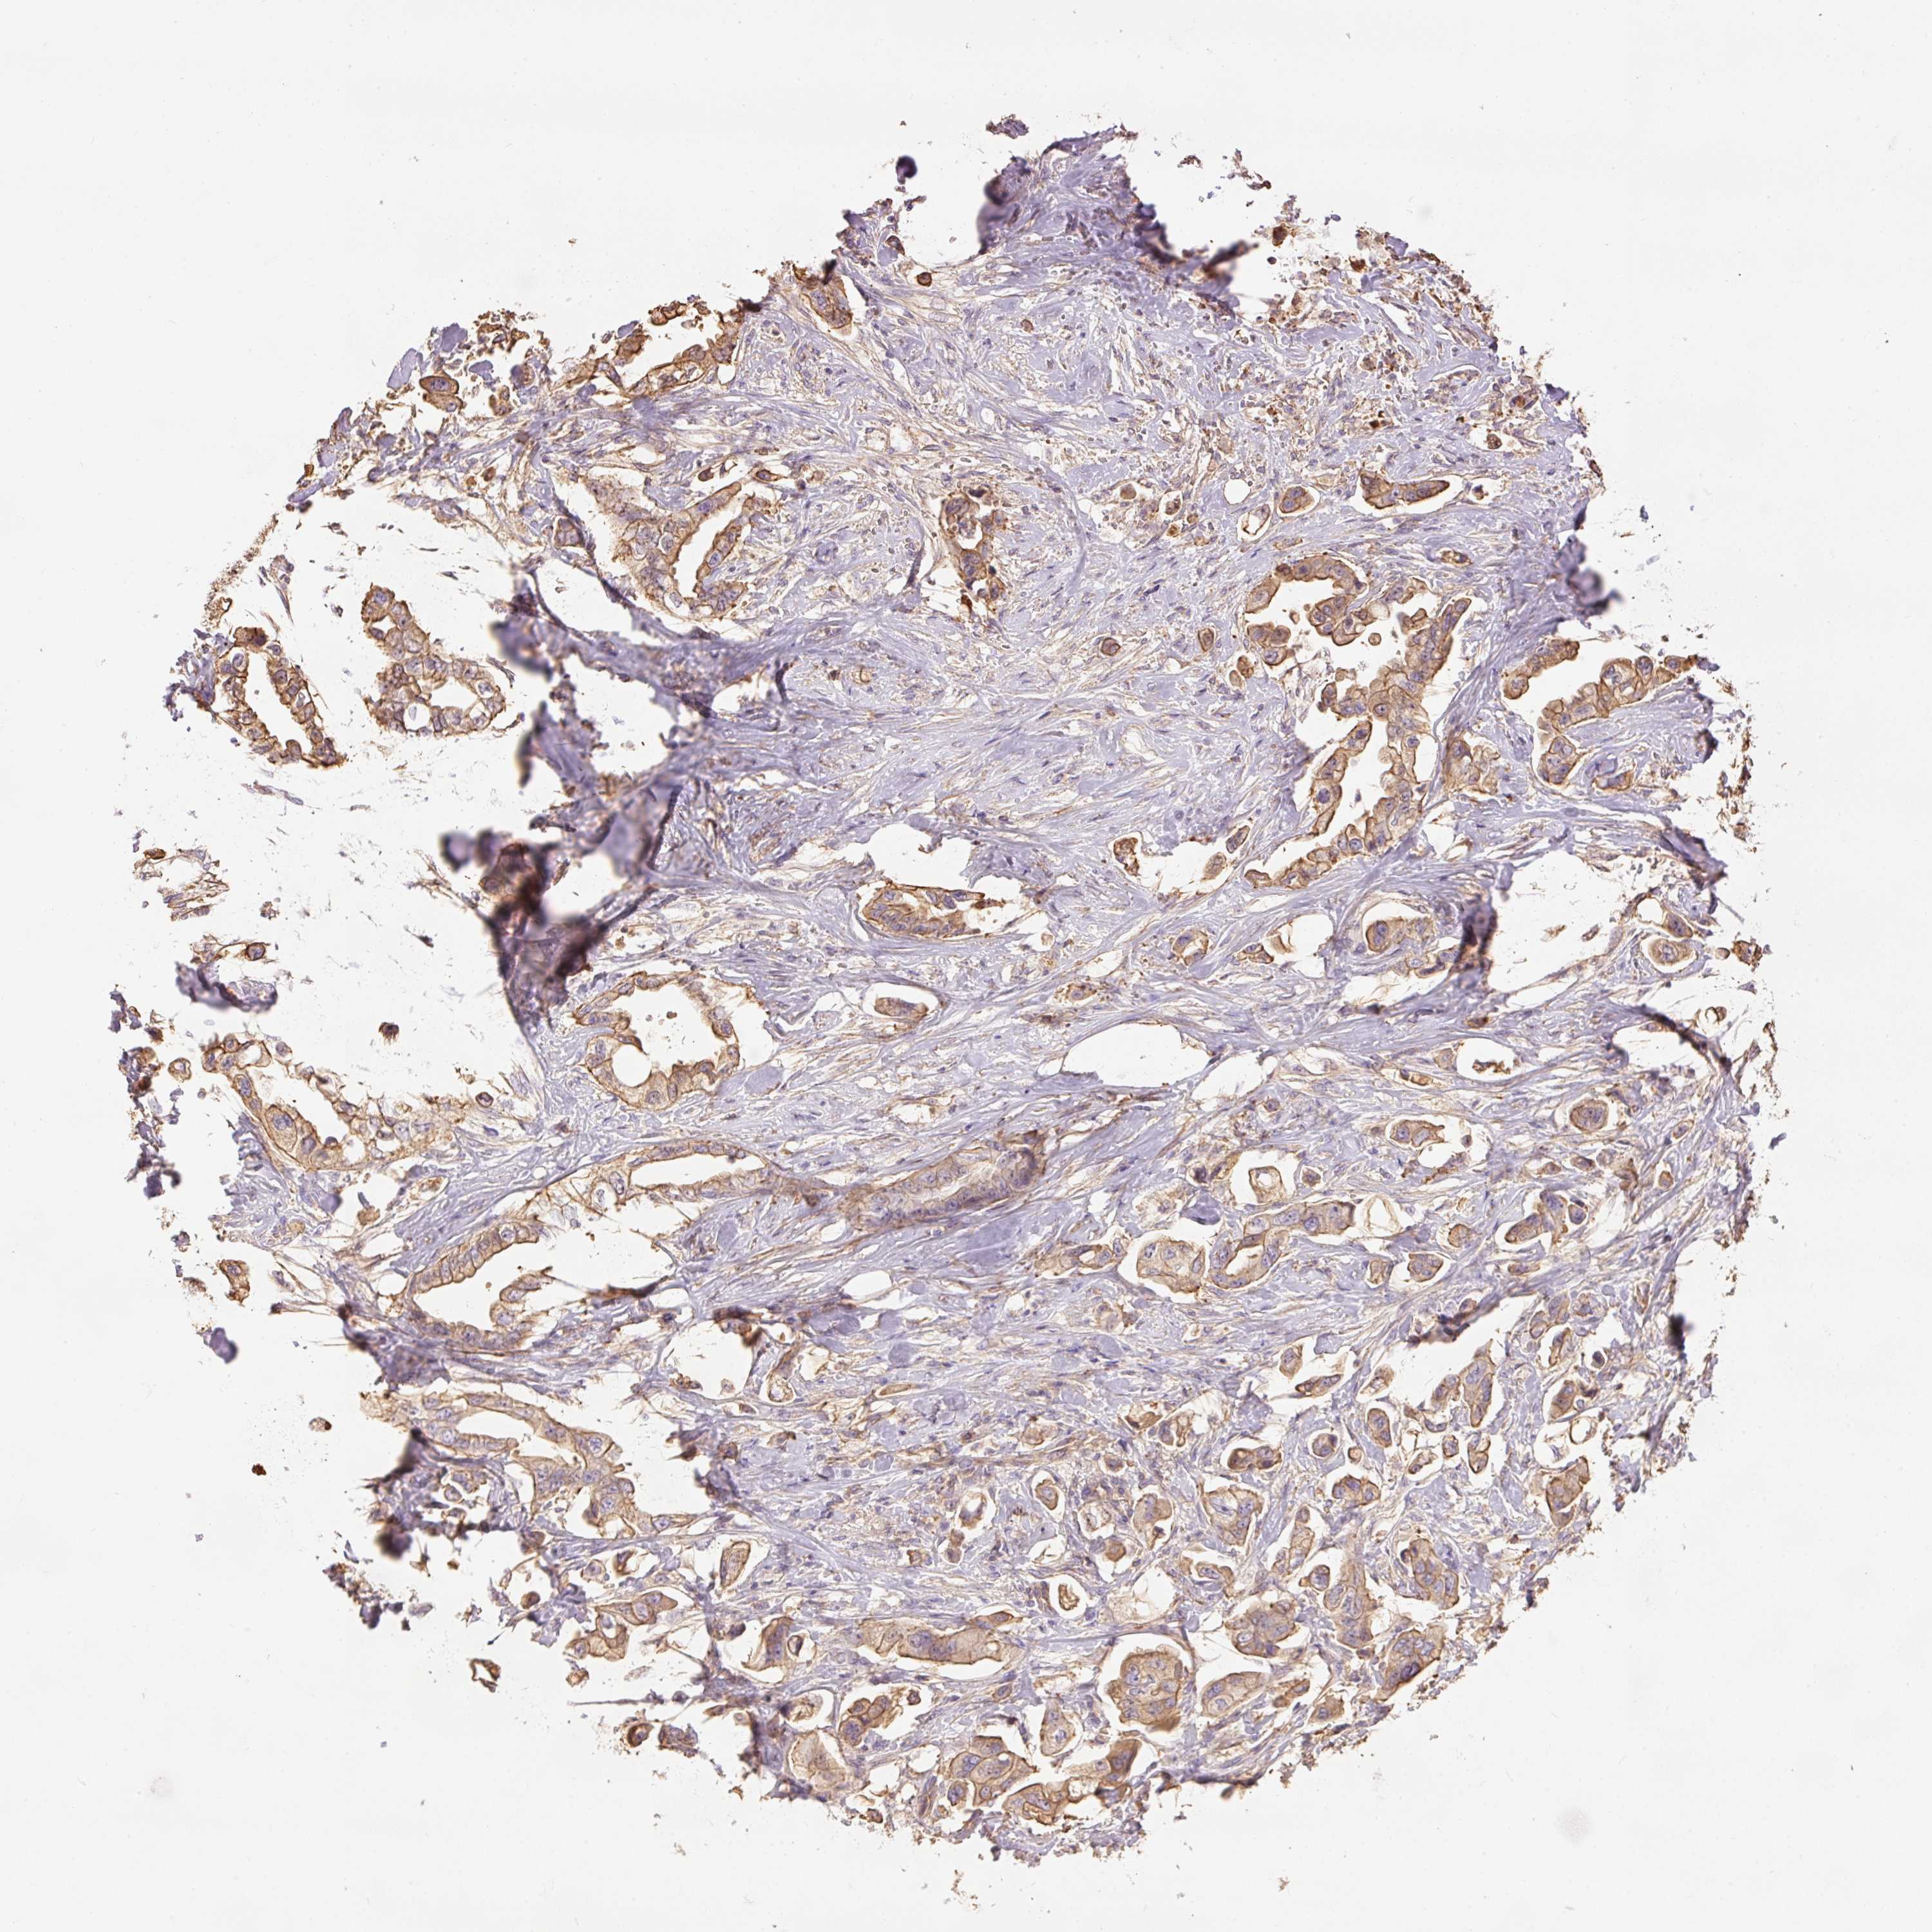

STOMACH CANCER - Protein expressioni

A mouse-over function shows sample information and annotation data. Click on an image to view it in a full screen mode. Samples can be filtered based on level of antibody staining by selecting one or several of the following categories: high, medium, low and not detected. The assay and annotation is described here.

Note that samples used for immunohistochemistry by the Human Protein Atlas do not correspond to samples in the TCGA dataset.

Antibody stainingi

Antibody staining in the annotated cell types in the current human tissue is reported as not detected, low, medium, or high, based on conventional immunohistochemistry profiling in selected tissues. This score is based on the combination of the staining intensity and fraction of stained cells.

Each image is clickable and will lead to virtual microscopy that enables deeper exploration of all samples and also displays staining intensity scores, fraction scores and subcellular localization as well as patient and tissue information for each sample.

Antibody HPA048630

Antibody HPA061142

Antibody CAB004026

Staining

High

Medium

Low

Not detected

Intensity

Strong

Moderate

Weak

Negative

Quantity

>75%

75%-25%

<25%

None

Location

Nuclear

Cytoplasmic/membranous

Cytoplasmic/membranous,nuclear

Adenocarcinoma, NOS

Adenocarcinoma, High grade